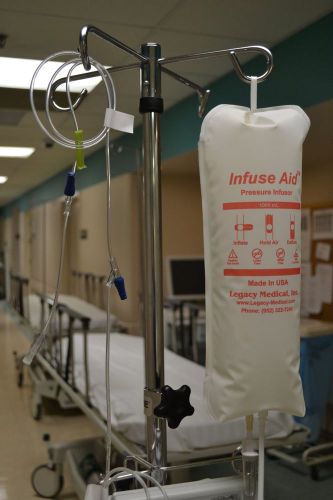

1000 mL Pressure Infuser Bag by Legacy Medical, Inc.

500 mL Infuse Aid Pressure Infuser Bag by Legacy Medical